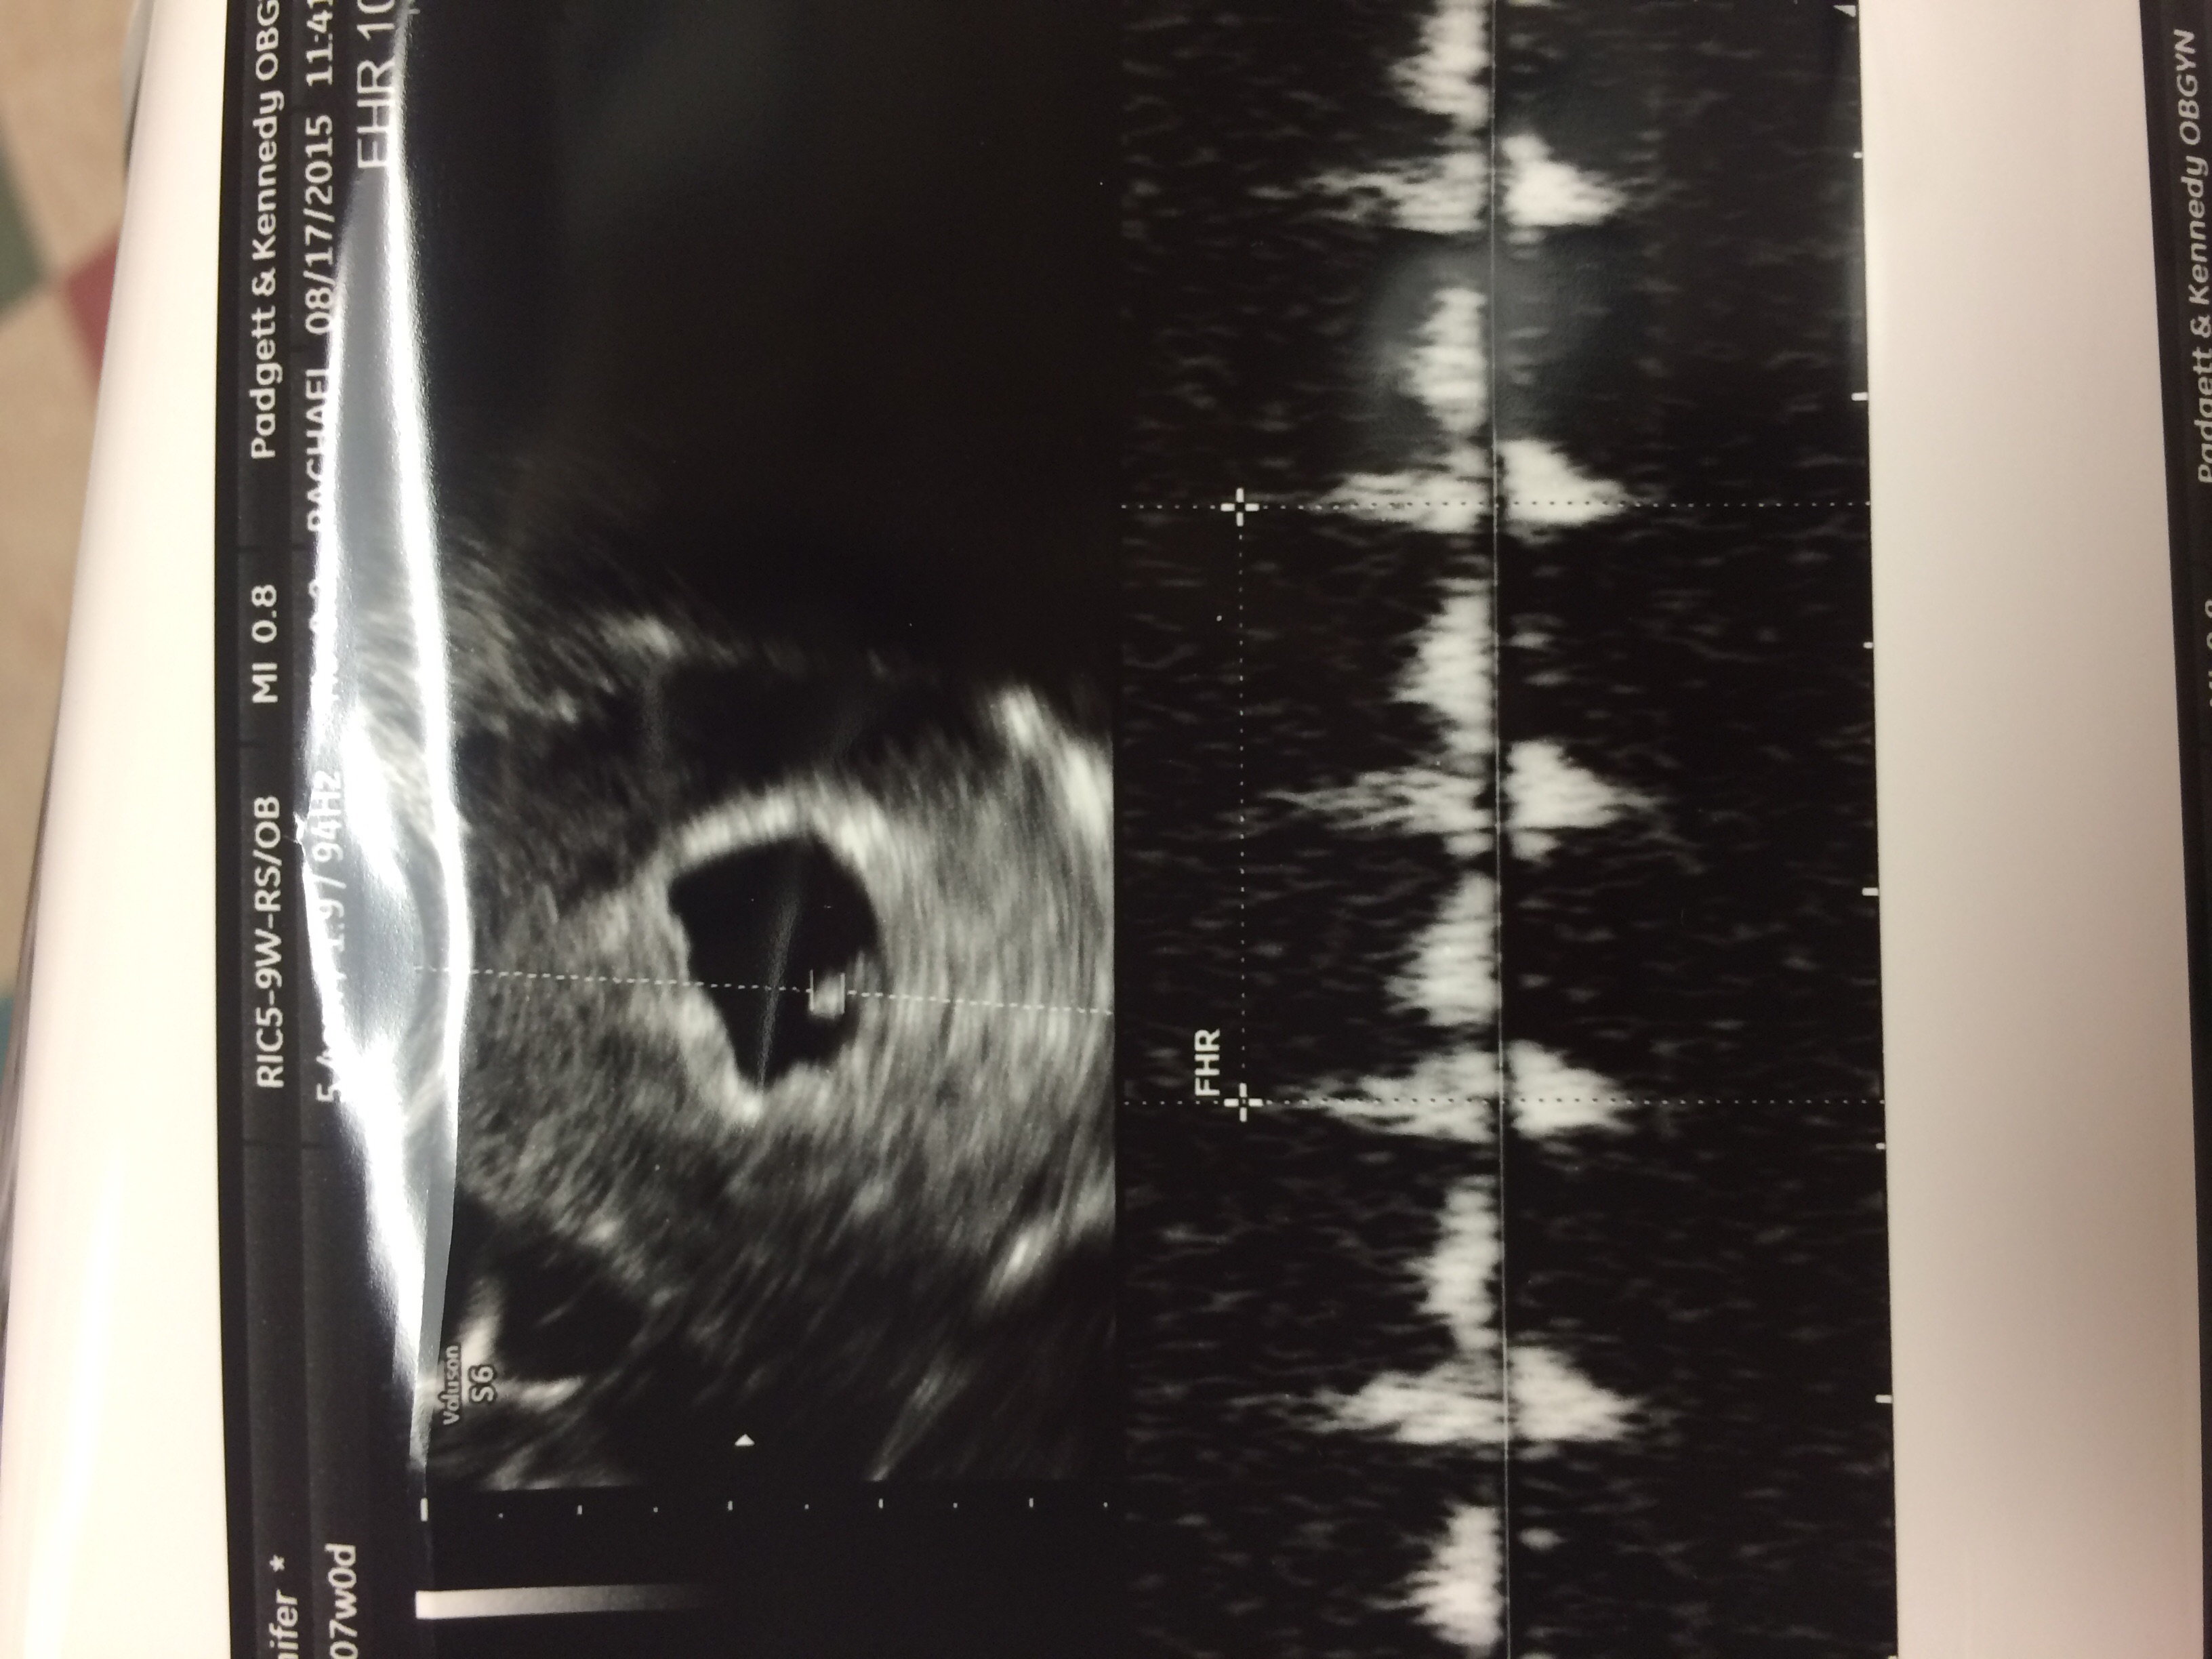

Here's ours! The ultrasound showed me being about 6w2d but they used my LMP which puts me at 7 weeks... The FHR was 100bpm. I thought it was a bit low but she said it was very stable and had a great rhythm! I'll get to have another in 4 weeks to hear it again! Such an amazing day!